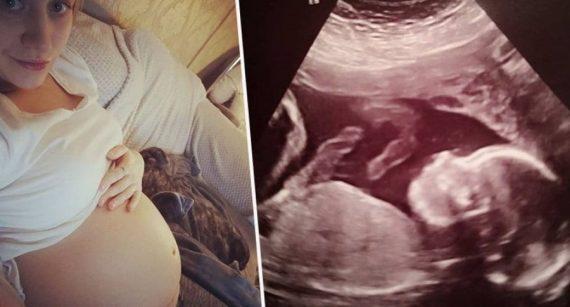

Το αγέννητο κοριtsάκι ήταν μόλις 20 εβδομάδων όταν το υπερηχογράφημα Β΄ επιπέδου της Μπέθαν Σίμπσον από το Έσσεξ εντόπισε ένα πρόβλημα που είχε στην σπονδυλική του στήλη.

Το έμβρυο είχε μια γενετική ανωμαλία, που ονομάζεται spina bifida (δισχιδής ράχη) η οποία επηρεάζει τον νωτιαίο μυελό και εμποδίζει τη σωστή ανάπτυξη.